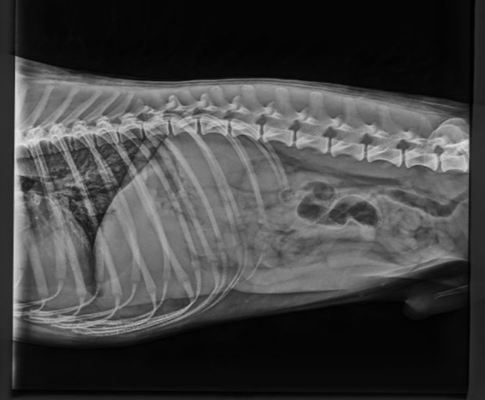

Spine

Spine testing in dogs is a fairly new concept in comparison to the other health tests available.

Spines are scored on three separate points:

Vertebral anomalies (VA)

Lumbosacral transitional vertebra (LTV)

Spondylosis (SP)

Each being scored from 0-4.

For those interested in testing Spines, we recommend the Finnish testing scheme INCOC for the most complete diagnosis.